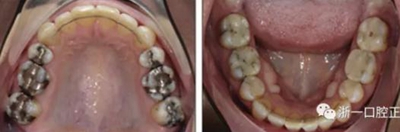

患者曾行正畸治療,現(xiàn)覺(jué)笑容不美觀前來(lái)就診。患者正面觀及側(cè)貌示下頜發(fā)育不足,偏高角,唇閉合不全。上下頜中線齊。覆合、覆蓋4毫米。磨牙關(guān)系及尖牙關(guān)系II類(lèi)。上頜擁擠度4mm,下頜擁擠度6mm。4顆第一前磨牙在第一次正畸治療時(shí)已拔除。上下牙弓呈尖圓型,牙弓狹窄。

因此最終,我們決定采用手術(shù)輔助快速擴(kuò)弓進(jìn)行上下頜擴(kuò)弓,上頜行腭中縫切開(kāi)術(shù)、下頜行正中劈開(kāi)后使用hyrax擴(kuò)弓器進(jìn)行擴(kuò)弓。擴(kuò)弓完成后再使用固定矯治器進(jìn)行矯正。

患者側(cè)貌改善,下唇唇肌緊張消失,上下唇可自然閉合。磨牙及尖牙關(guān)系糾正至I類(lèi),覆合覆蓋正常。上下頜弓型糾正至卵圓形,牙弓寬度增加。頭影測(cè)量分析示SNA角81.8°,ANB角3°。頭影測(cè)量重疊圖示下頜骨向后旋轉(zhuǎn),垂直面高度略有增加。